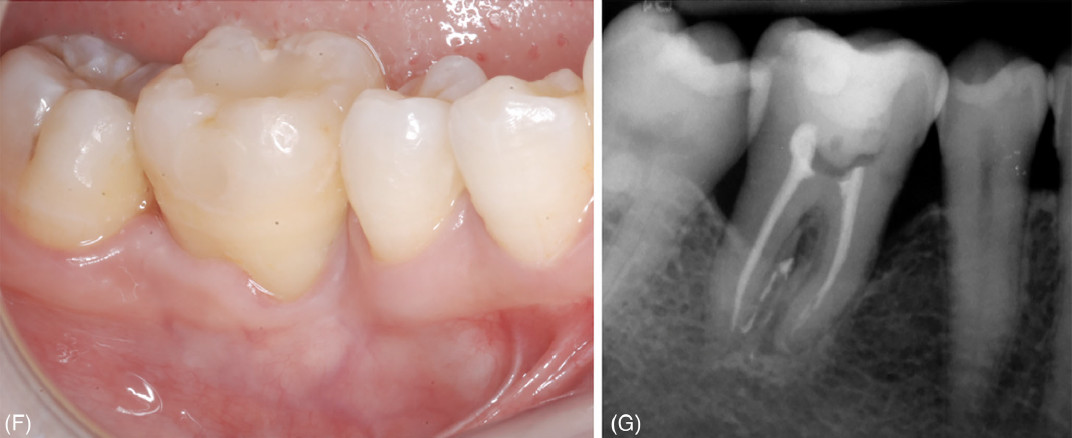

Фото 2. Удаление зуба 46 и его замещение с использованием зуба 48. (F) Клиническое обследование через 24 месяца наблюдения. (G) Прицельная рентгенограмма через 24 месяца наблюдения

Фото 3. Удаление зуба 16 и его замещение с использованием зуба 18. (A) Лунка после удаления зуба 16. (B) Выраженная потеря костной ткани на щечной поверхности реципиентного участка. (C) Донорский зуб сразу после его удаления. (D) Клиническая картина сразу после операции и шинирования донорского зуба. (E) Рентгенологическая картина сразу после операции и шинирования донорского зуба

Фото 3. Удаление зуба 16 и его замещение с использованием зуба 18. (F) Клиническая картина через 24 месяца; зондирование показывает, что значительная часть щечного прикрепления, отсутствовавшая при первом визите, восстановилась. (G) Рентгенологическая картина через 24 месяца

Удаление зубов 16 и 18 также выполнялось щипцами; зуб 18 был немедленно трансплантирован в РУ с расположением его ЦЭГ на том же уровне, что и ЦЭГ соседних зубов, после чего был наложен шов.

В обоих случаях для стабилизации ДЗ применялось полужёсткое шинирование зуба (выполненное с использованием композитной смолы с ортодонтической проволокой или без неё), а все окклюзионные контакты были устранены алмазным бором.

При контрольном визите через 24 месяца подвижность и фуркационные поражения выявлены не были; значения глубины зондирования ≤ 4 мм были зафиксированы во всех точках обоих донорских зубов. Рентгенологических признаков резорбции корня, анкилоза или периапикальных/ периодонтальных очагов поражения обнаружено не было; уровень костной ткани у обоих донорских зубов составил более 50% длины корня.